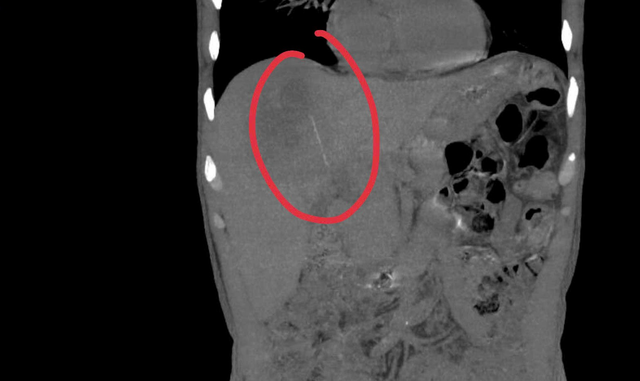

Qua thăm khám ban đầu, bệnh nhân được chỉ định siêu âm ổ bụng và phát hiện có ổ áp-xe gan. Khi tiến hành siêu âm kỹ hơn, ê kíp phát hiện một dị vật cản quang xuyên trong nhu mô gan, chiều dài ước tính khoảng 6-7cm. Ngay sau đó, bệnh nhân được chỉ định chụp cắt lớp vi tính (CT scan) ổ bụng. Kết quả cho thấy có một dị vật dạng que dài nằm hoàn toàn trong nhu mô gan, kèo theo ổ áp xe sâu. Trước nguy cơ biến chứng nặng nếu không điều kịp thời, ê kíp khoa Nội tiêu hóa đã nhanh chóng hội chẩn cùng khoa Ngoại Gan Mật Tụy, thống nhất phương án phẫu thuật lấy dị vật, dẫn lưu ổ áp xe, kết hợp điều trị kháng sinh phù hợp.

Hình ảnh CT Scan ổ bụng của bệnh nhân. Ảnh: BVCC.